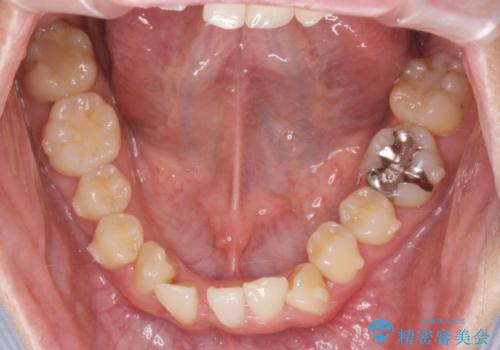

ねじれ・がたつきのある前歯を改善

- がたつき・すれ違い、ねじれのある前歯の見た目、噛み合わせの改善を希望され来院されました。

4本の小臼歯抜歯を避け、下顎前歯の1本抜歯の極力少ない抜歯本数で審美的な歯並びを得る治療計画としました。

すれ違いを治すのが得意な前歯部の部分ワイヤーを用いることで、治療期間を短縮することができました。